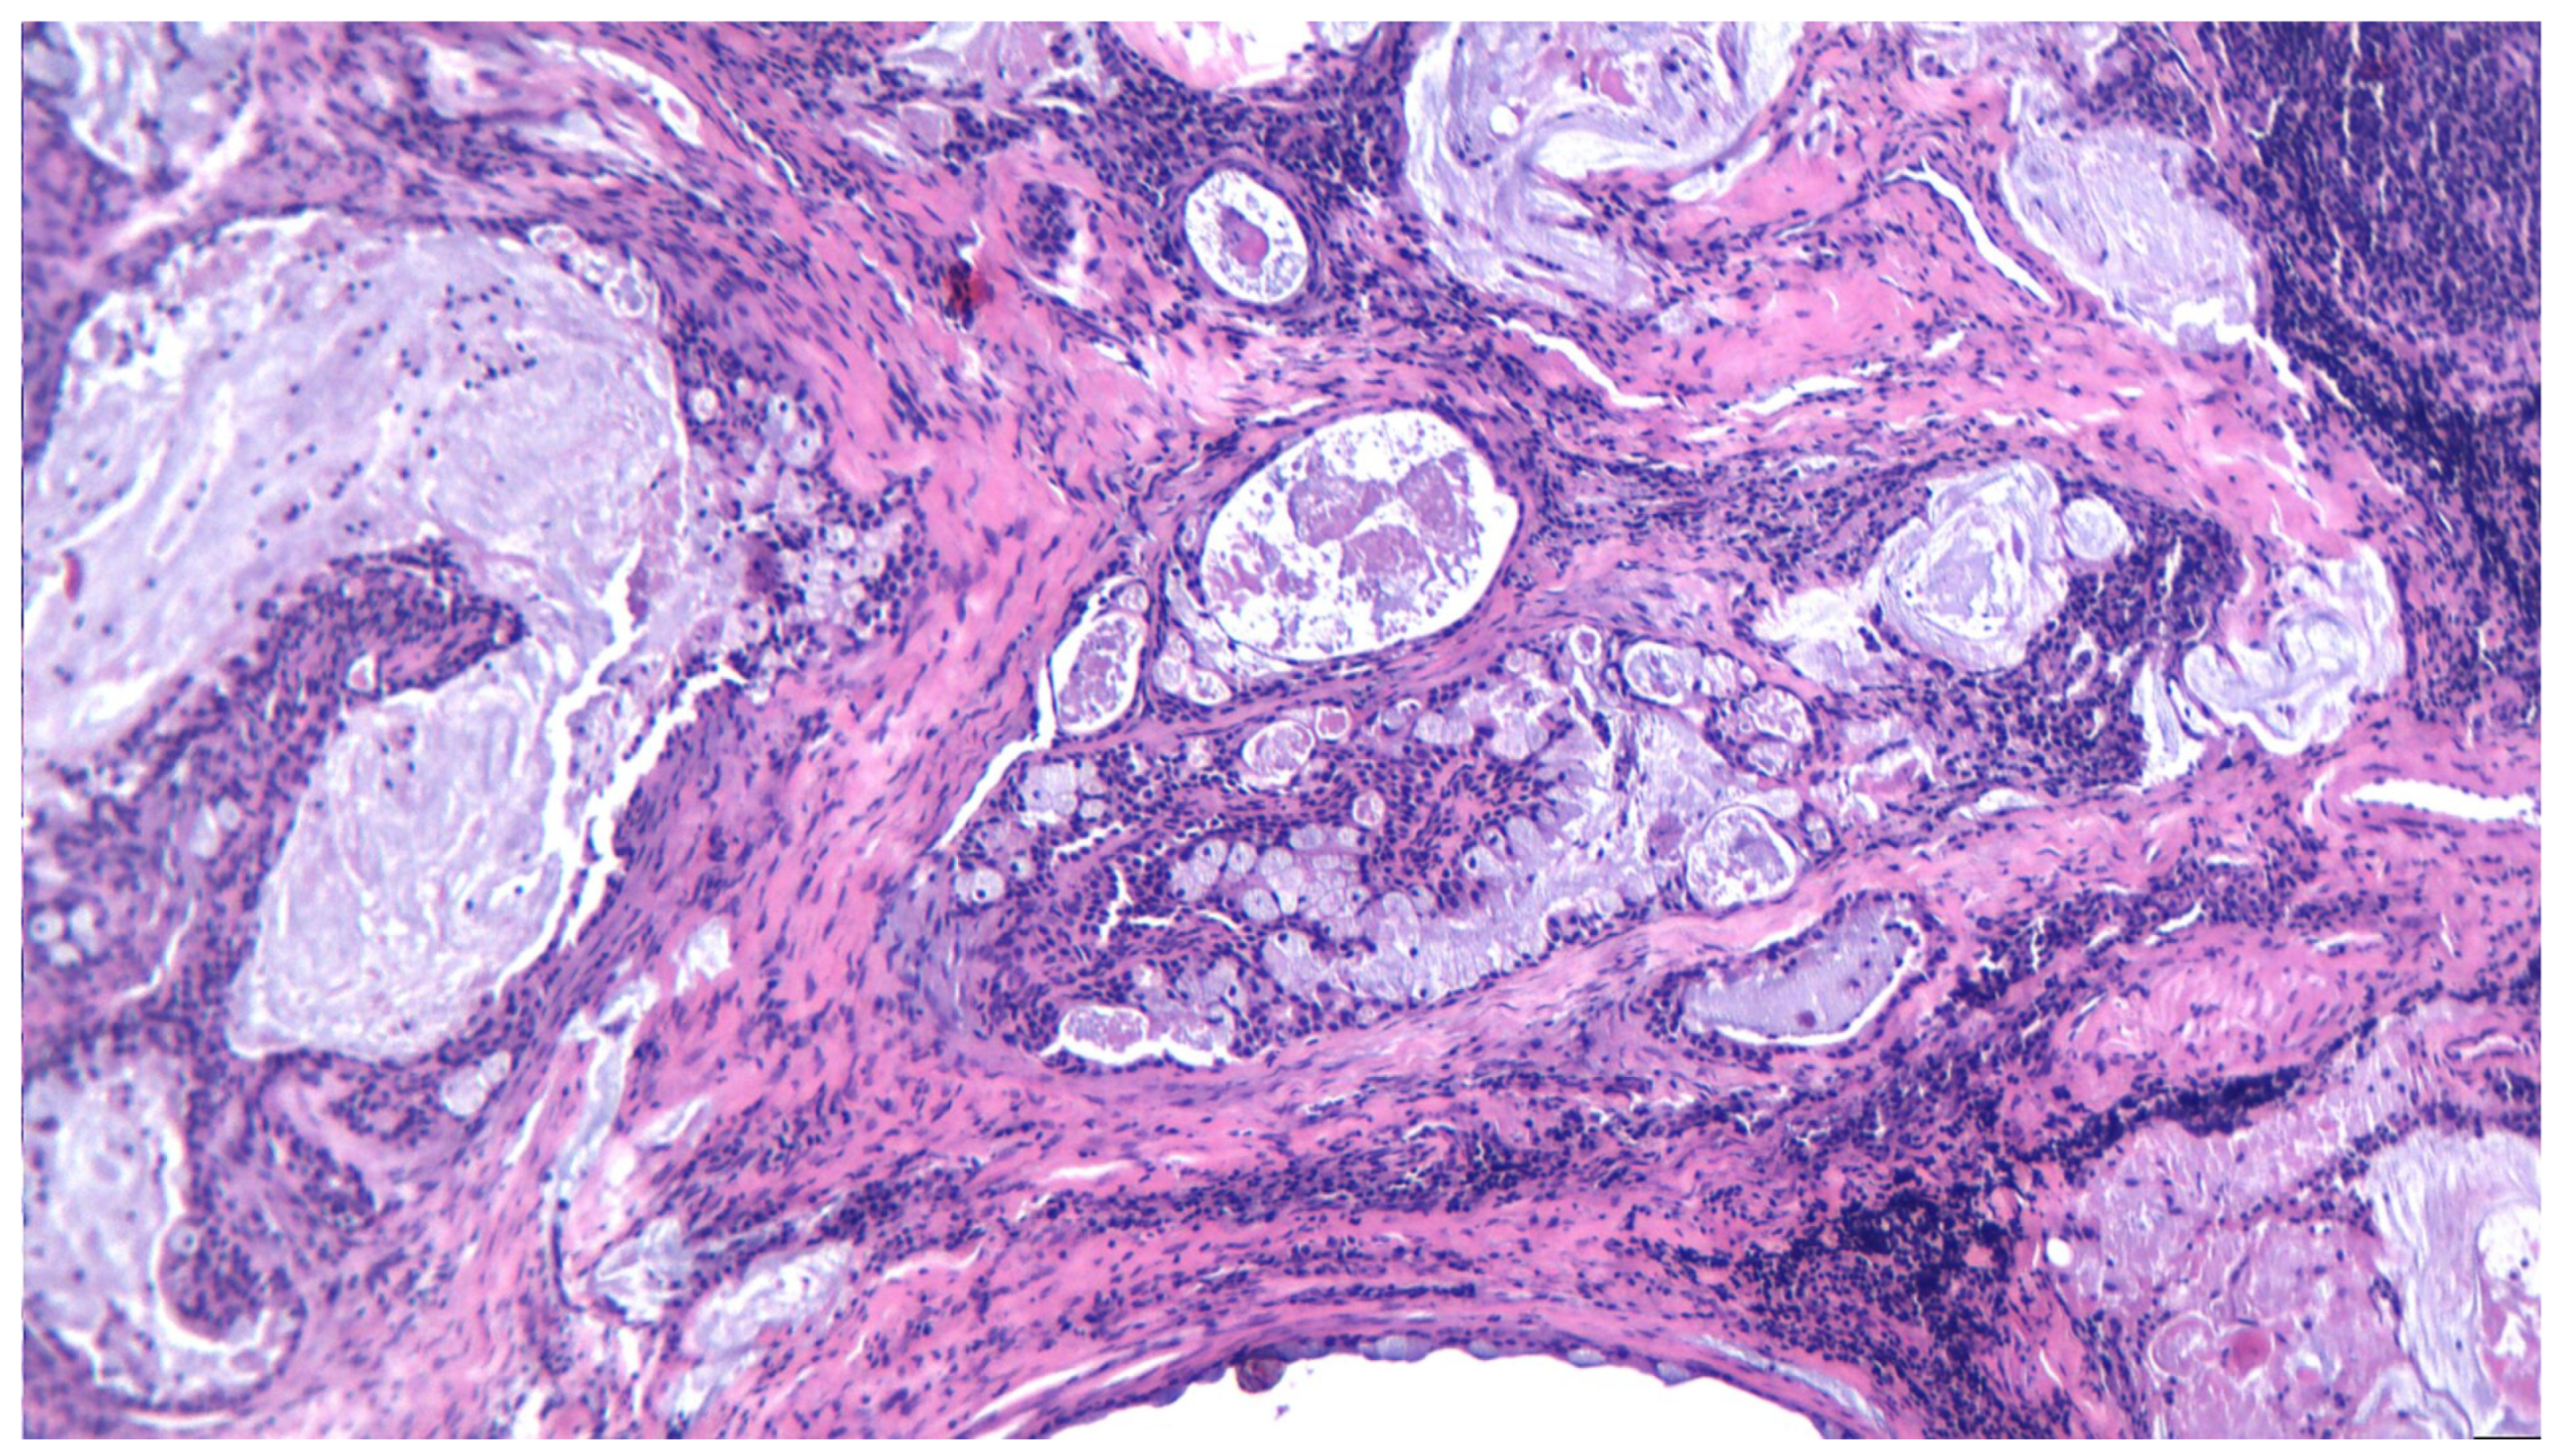

3.10. Adenocarcinoma